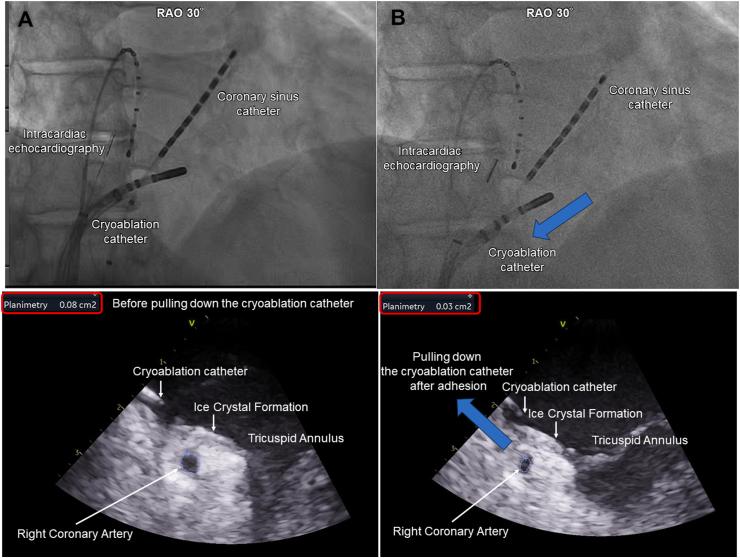

Radiofrequency (RF) catheter ablation is the primary treatment for cavotricuspid isthmus (CTI)-dependent atrial flutter (AFL), with cryothermal energy as an alternative. While cryoablation offers comparable effectiveness and safety to RF ablation, it poses a risk of coronary artery spasm leading to ST-elevation. This case report presents a 65-year-old man with drug-refractory atrial fibrillation (AF) and AFL undergoing cryothermal CTI ablation guided by intracardiac echocardiography (ICE). During the procedure, two distinct ST-elevation episodes were observed. The first episode coincided with the pull-down of the cryoablation catheter, potentially resulting in coronary compression, as indicated by ICE, and was rapidly resolved by discontinuing the freezing process. The second episode, occurring without active freezing, was attributed to coronary artery spasm and resolved with intracoronary nitroglycerin administration. During the second episode, emergent right coronary angiography confirmed total occlusion in the segment 4 AV adjacent to the region where cryoablation was performed, which fully resolved post-nitroglycerin. This report underscores the dual mechanisms of ST-elevation-coronary artery compression and spasm-during cryothermal CTI ablation, highlighting the critical role of ICE in enhancing procedural safety.

射频(RF)导管消融术是三尖瓣峡部(CTI)依赖性心房扑动(AFL)的主要治疗方法,冷冻热能消融可作为替代方案。虽然冷冻消融与射频消融具有相当的有效性和安全性,但它存在导致冠状动脉痉挛进而引起ST段抬高的风险。本病例报告介绍了一名65岁患有药物难治性心房颤动(AF)和AFL的男性,在心脏内超声心动图(ICE)引导下接受冷冻CTI消融术。术中观察到两次明显的ST段抬高发作。第一次发作与冷冻消融导管下拉同时发生,心脏内超声心动图显示这可能导致冠状动脉受压,通过停止冷冻过程迅速得到缓解。第二次发作在未进行主动冷冻时发生,归因于冠状动脉痉挛,通过冠状动脉内给予硝酸甘油得以缓解。在第二次发作期间,急诊右冠状动脉造影证实,在进行冷冻消融区域相邻的4 AV节段完全闭塞,使用硝酸甘油后完全缓解。本报告强调了冷冻CTI消融术中ST段抬高的双重机制——冠状动脉受压和痉挛,突出了心脏内超声心动图在提高手术安全性方面的关键作用。